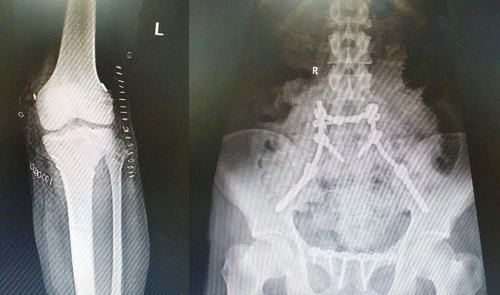

نجح الفريق الطبي بمستشفى د. سليمان الحبيب بالقصيم بفضل من الله، بالتدخل السريع لإنقاذ حياة شاب يبلغ من العمر 21 عاماً إثر تعرضه لحادث سير مروع، تسبب في إصابته بنزيف حاد وكسور في الجهة الأمامية والخلفية من الحوض، وكسر متفتت في الفقرة العجزية أدت إلى انفصال الحوض عن العمود الفقري مع ضغط شديد على الأعصاب في منطقة الفقرات القطنية السفلي، بالإضافة إلى خلع كامل في الركبة اليسرى وقطع في الأربطة من الجهة الخارجية والرباطين المتصالبين الأمامي والخلفي للركبة اليسرى.

وعن حالة المريض قال رئيس الفريق الطبي المعالج الدكتور علاء الحمدان استشاري جراحة العظام والمفاصل الحاصل على الزمالة الألمانية، إن استشاريي الطوارئ بالمستشفى تعاملوا سريعاً مع حالة المريض المتدهورة، حيث تم إجراء كافة الإسعافات الأولية لوقف النزيف، وعمل الفحوصات المخبرية والإشعاعية والتي أظهرت هبوط بالدورة الدموية ونقص في نسبة الأكسجين مع فقدان تام للوعي ونزيف حاد بالبطن، بالإضافة إلى الكسور آنفة الذكر وخلع الركبة اليسرى».

وأضاف: «تم تشكيل فريق طبي مكون من استشاريي الطوارىء والعناية الحرجة والعظام والجراحة العامة والمخ والأعصاب والتخدير لمباشرة حالة المريض ووضع الخطة العلاجية المناسبة، حيث تقرر إجراء عدة عمليات، خضع في الأولى التي أشرف عليها الدكتور غالب عابد استشاري الجراحة العامة لعملية استكشافية للبطن، كما شارك في هذه العملية الدكتورعادل الطويرقي استشاري المسالك البولية بإجراء عملية استكشافية للمثانة البولية والتأكد من سلامة جدارها من الإصابات»، بعد ذلك خضع لعملية كبيرة بمشاركة الدكتور ناجي المسعود استشاري المخ والأعصاب، تم خلالها علاج كسور وتهتك الحوض الذي كان منفصلاً تماماً عن العمود الفقري، وكانت آخر العمليات التي خضع لها عملية إعمار الرباط المتصالب الأمامي والرباط المتصالب الخلفي بواسطة المنظار، بالإضافة إلى ترميم الرباط الخارجي والأنسجة المقطوعة من الجهة الخارجية مع إزالة الضغط عن العصب الذي يمر في الجهة الخارجية من الركبة ويغذي عضلات الكاحل والقدم.